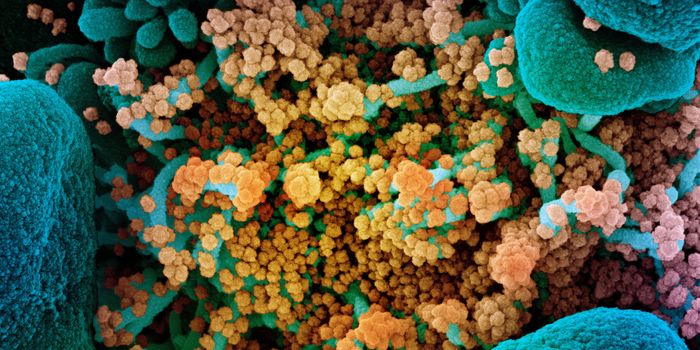

DEC 07, 2021Clinical & Molecular DXMore mutations, more transmissible, and more likely to infect vaccinated people—coronavirus variants such as Omicr ...